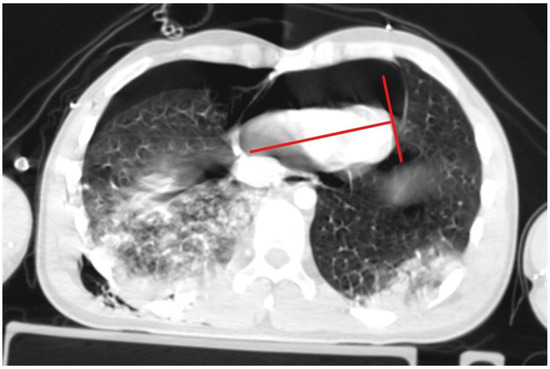

A patient with blunt trauma may have several severe injuries; each of them, if untreated, can be fatal. A post-mortem examination of patients after falls from heights did not reveal the presence of isolated pneumopericardium; it was always accompanied by other severe injuries [5]. The clinical picture of increasing pneumopericardium may be confused by concurrent conditions: cardiac contusion, pneumothorax, hemorrhage, or spinal shock [20]. Initially, our patient presented symptoms that could suggest both tension pneumothorax and tension pneumopericardium. Bedside ultrasonography revealed two significant symptoms: the absence of pleural sliding on the right side of the chest and the lack of heart image in the available ultrasound imaging windows. Cheryl L. Reid et al. [21] in 1983 described the characteristic signs of pneumomediastinum and pneumopericardium as an “air gap sign”. This symptom involves the cyclic appearance of air echoes, thus covering the image of the heart during systole and early phase of diastole of ventricles. It is caused by a physical shift and a reduction in the volume of air due to changes in the volume of the ventricles during the heartbeat [21,22], but this symptom does not occur in cases of tension pneumopericardium because elevated pressure in the pericardium keeps the heart under the layer of air. Due to the more frequent occurrence of tension pneumothorax compared to tension pneumopericardium, drainage of the right pleural cavity was performed, achieving the initial improvement in the patient’s condition, which allowed for performing CT scanning in the polytrauma protocol, where symptoms of tension pneumopericardium were seen. Heimer et al. [5] stated “ballooning” as a typical sign of tension pneumopericardium in CT scanning, which involves the protrusion of the pericardium beyond the line drawn of the apex of the heart and perpendicular to its axis, as shown in Figure 4. If the pericardium does not pass beyond this line, the pneumopericardium is considered normotensive.

Figure 4. Ballooning is a sign of tension pneumopericardium.